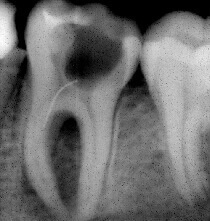

Probleem. Sügav karioosne õõnsus

Lahendus. Kanalid puhastati, valmistati ette täidiseks ja tehti hambaravifoto koos täitematerjaliga.

Sulge hamba juurekanalid. Hammas on valmis edasiseks raviks.